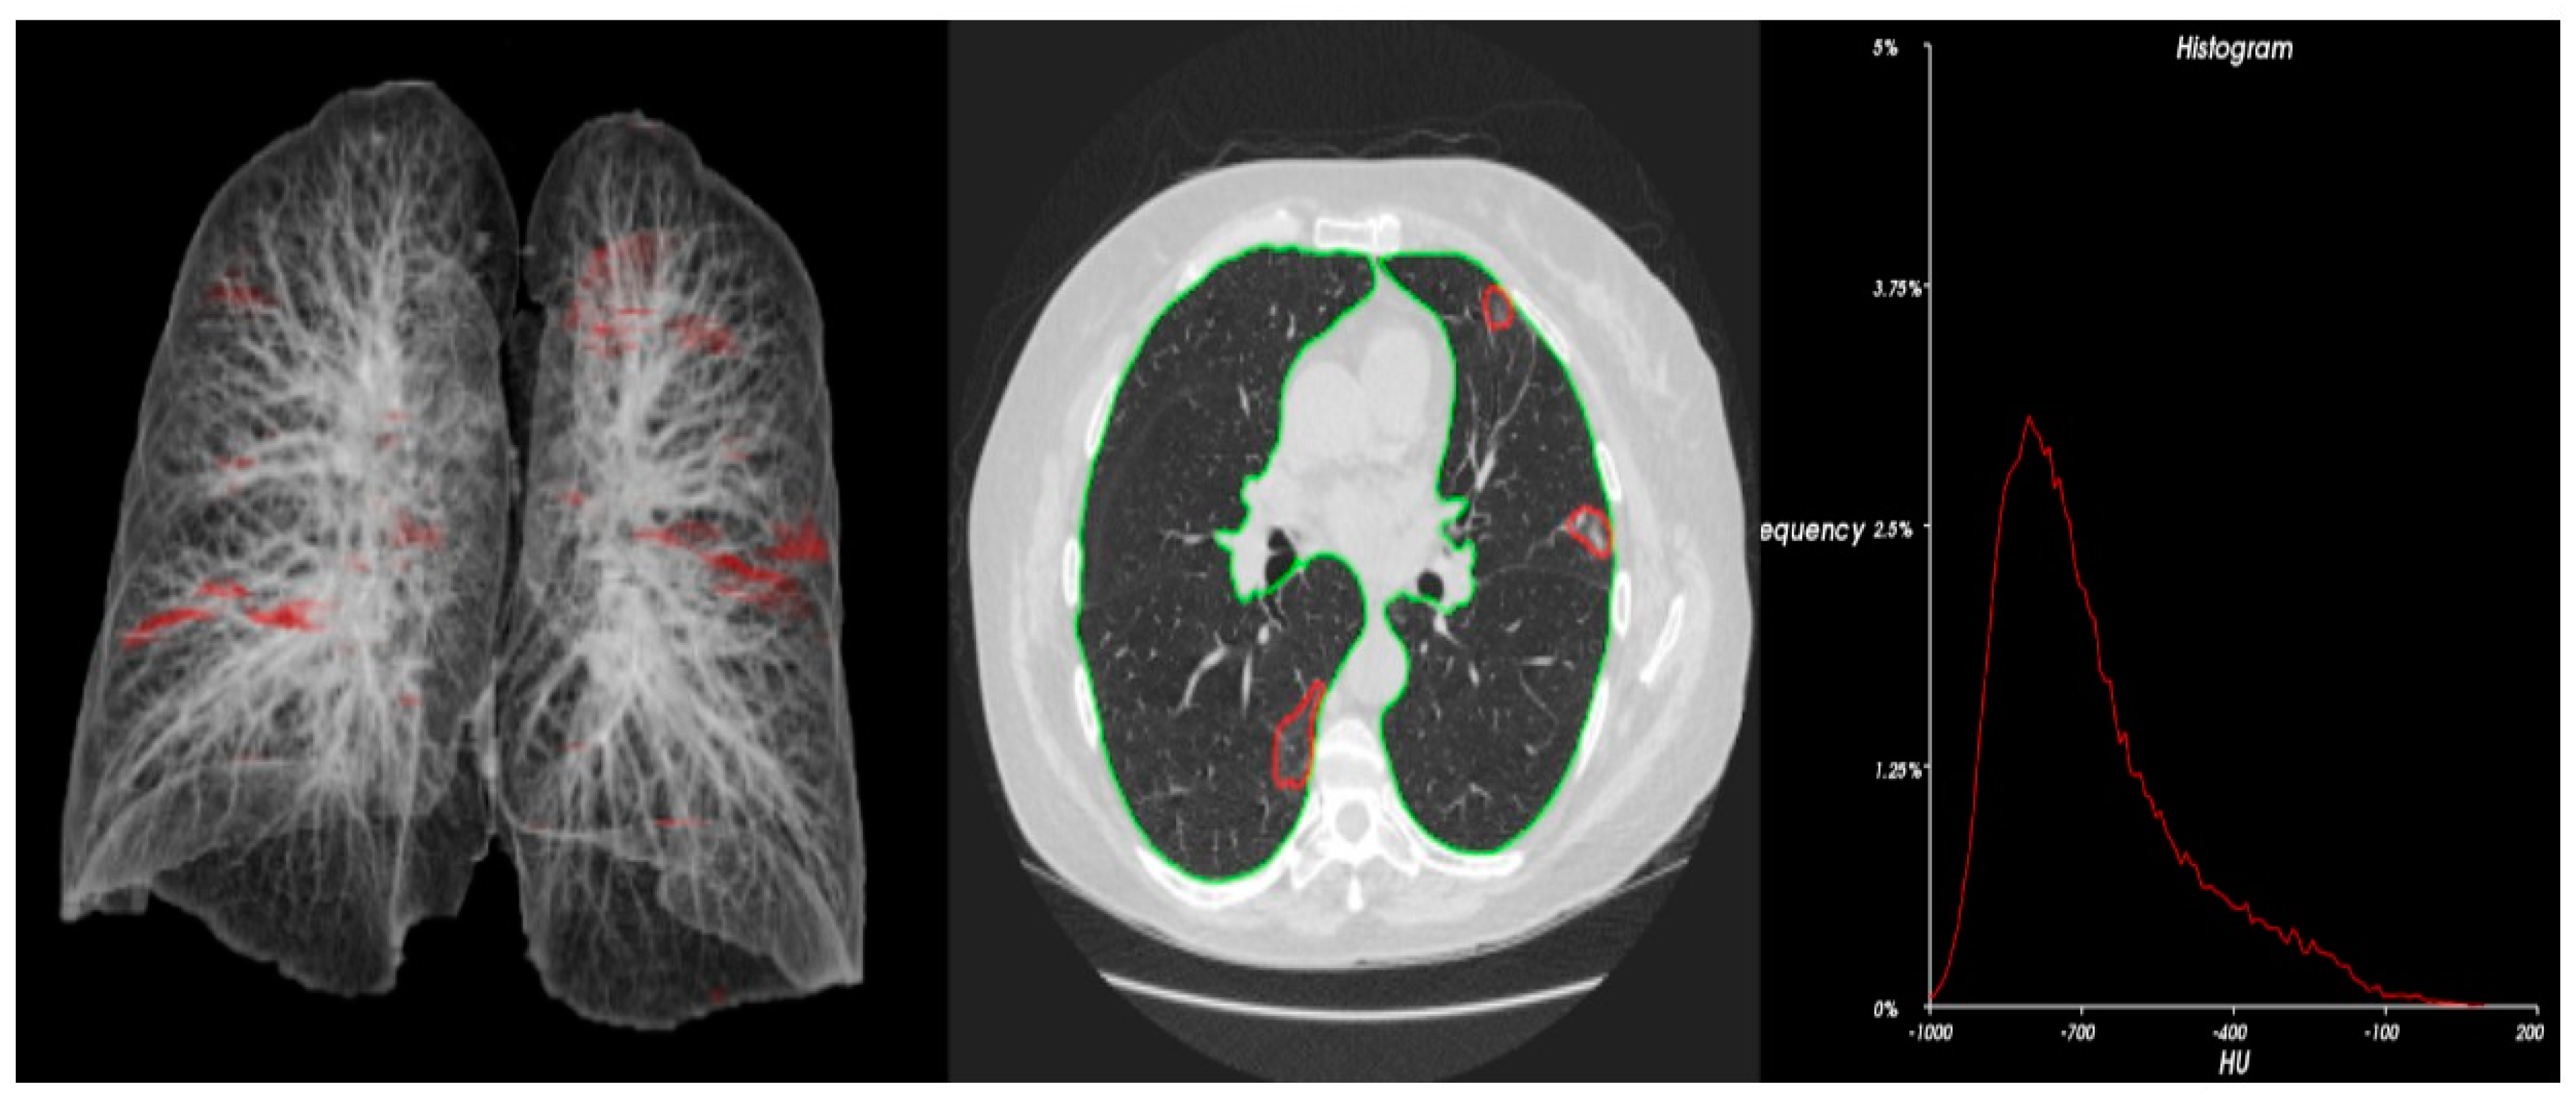

2.2. Study Procedure

2.3. Methods

2.4. Statistics and Data Analysis

3. Results